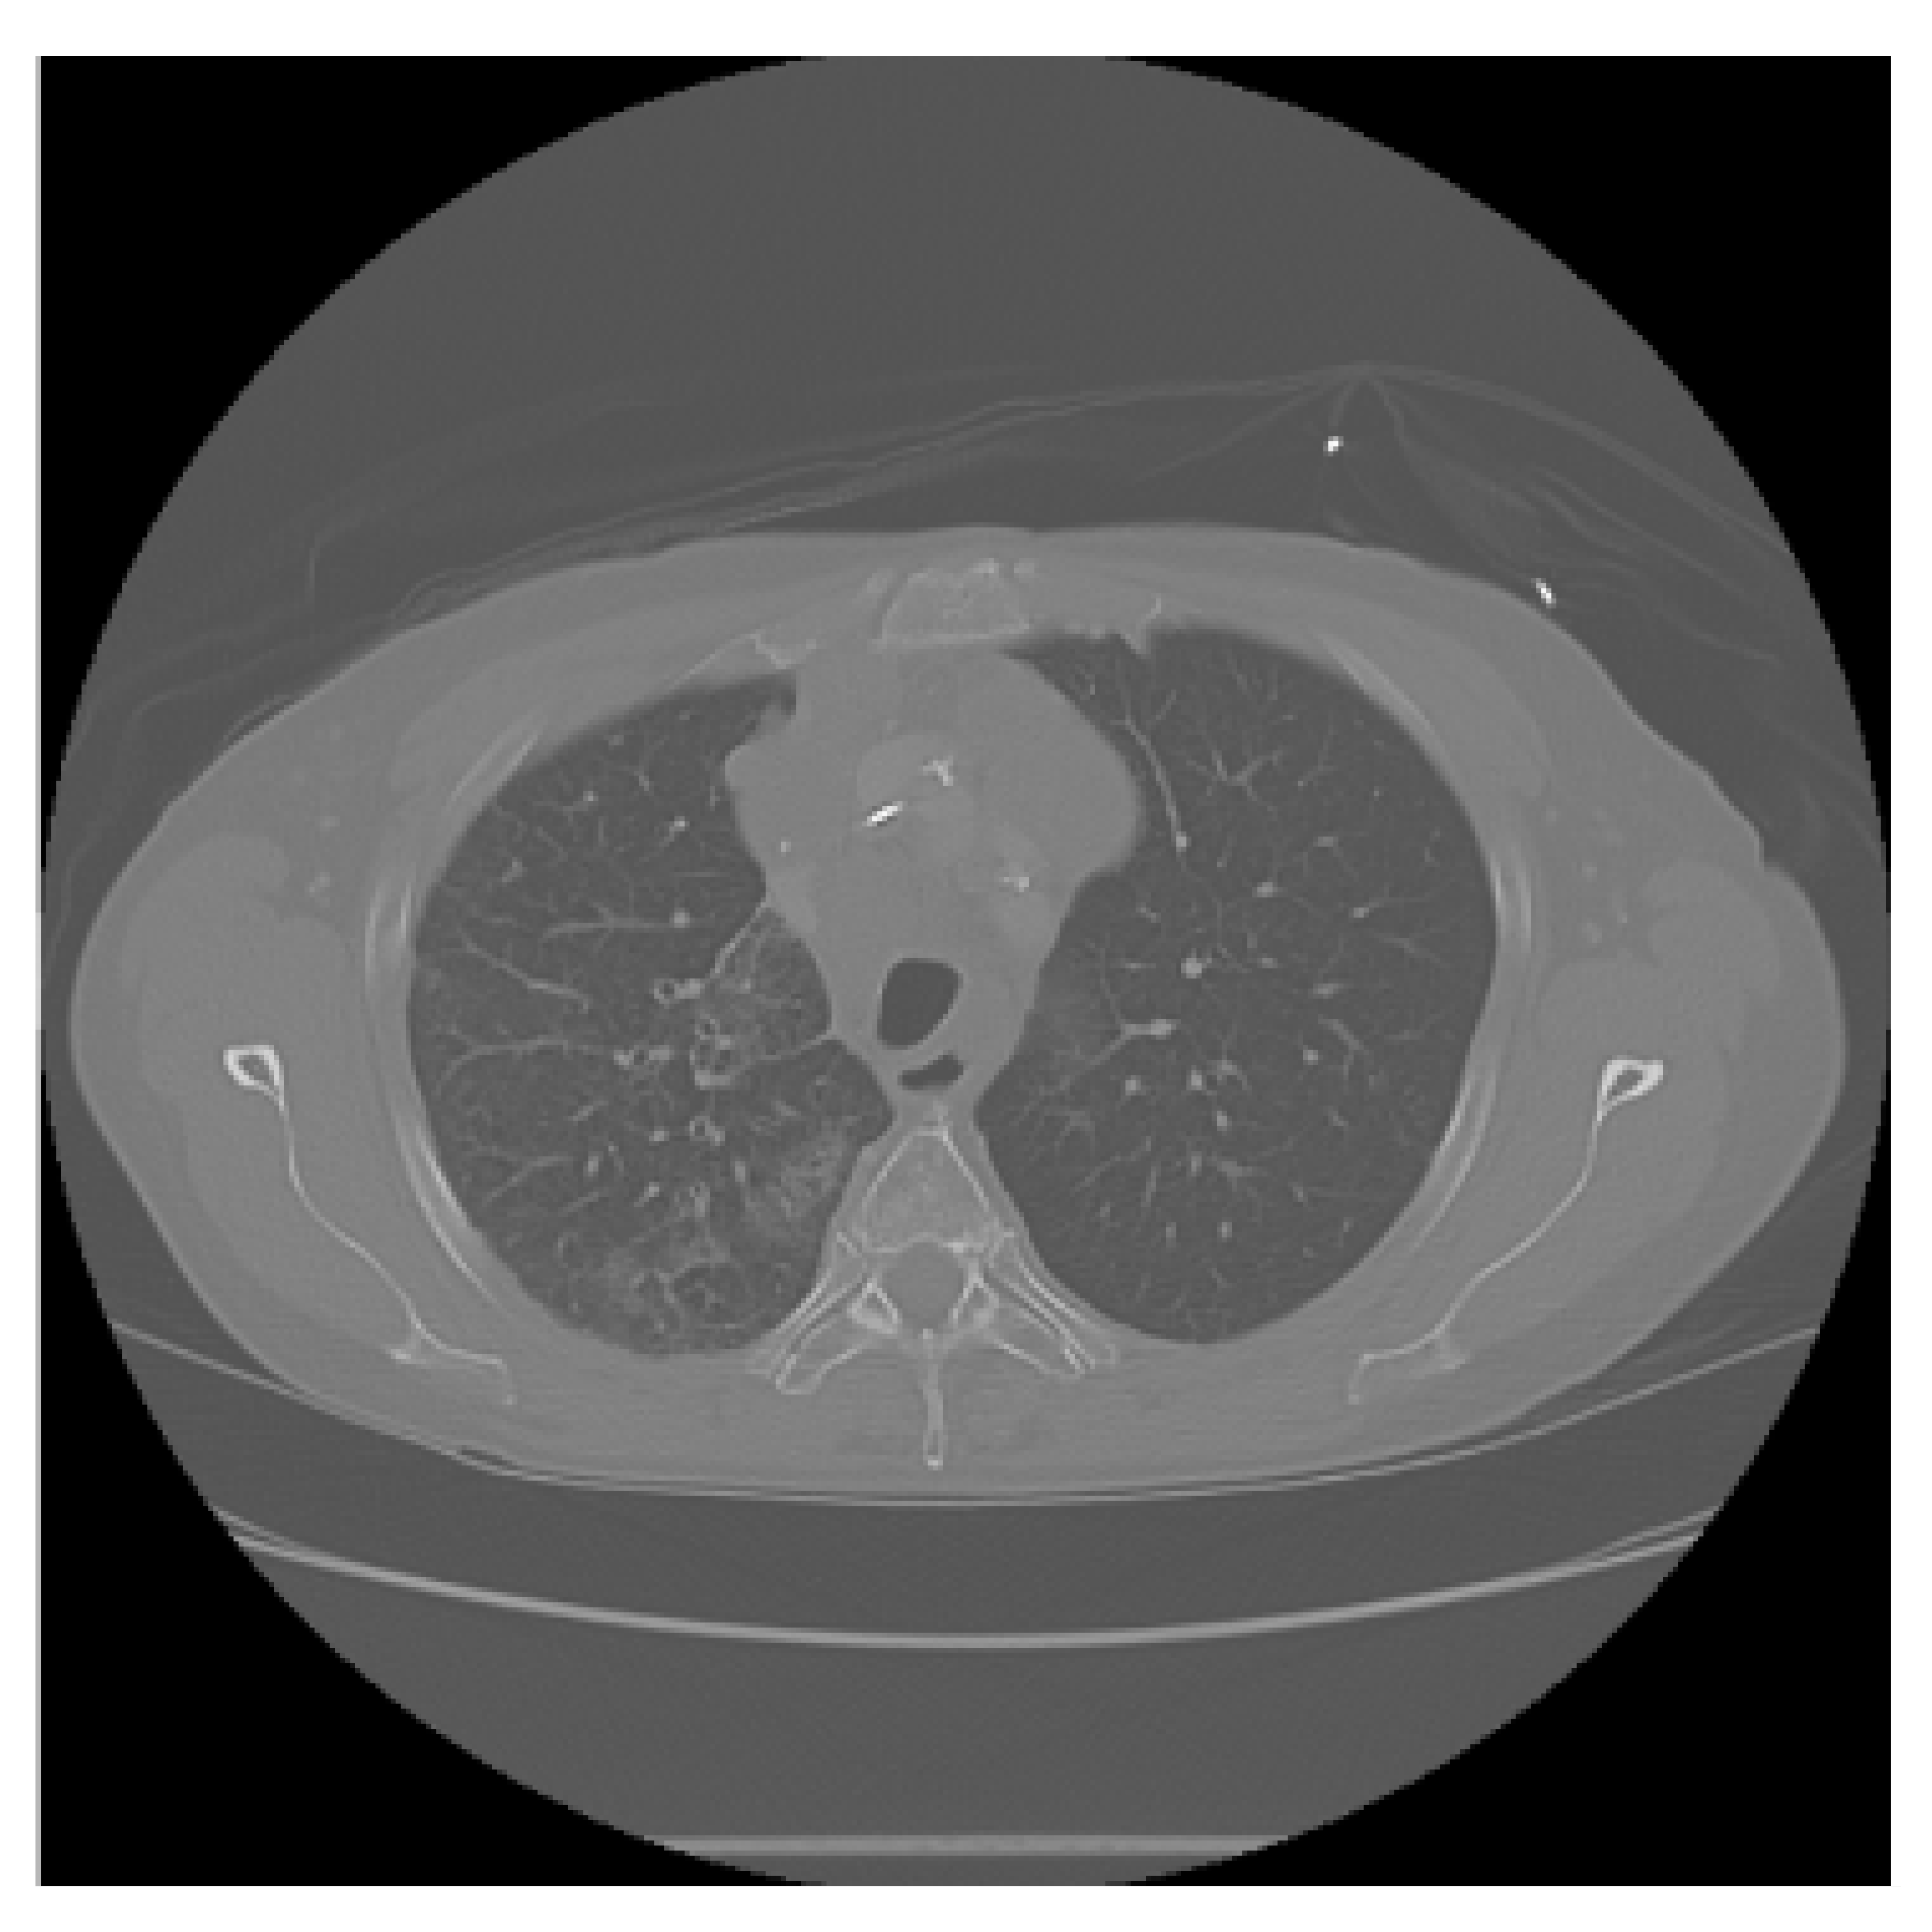

The APILungCancer interface provides intuitive functionality for loading and analyzing DICOM medical images. In the Load DICOM Images section, users can select and process CT scans for lung cancer evaluation. Once an image is loaded and analysis is performed, the software presents a visualization of the image along with the predicted probability of cancer (Table 7). Our study focused on lung cancer, including subtypes such as adenocarcinoma, squamous cell carcinoma, and small cell carcinoma. About 1000 training images and 300 test images from the CMB-LCA dataset were used to develop and validate the system.

In this example (Figure 5), the DICOM image 1-27.dcm from the test set was processed and the software calculated a cancer probability of 0.4267 (42.67%), indicating a high likelihood of malignancy.

Figure 5.

Determination of the probability of lung cancer. Example output of the system for the image 1-27.dcm, yielding a predicted probability of 42.67%, consistent with Table 7.

This value matches the result in Table 7, confirming the consistency of the predictions generated by the AI-based model integrated into the system.